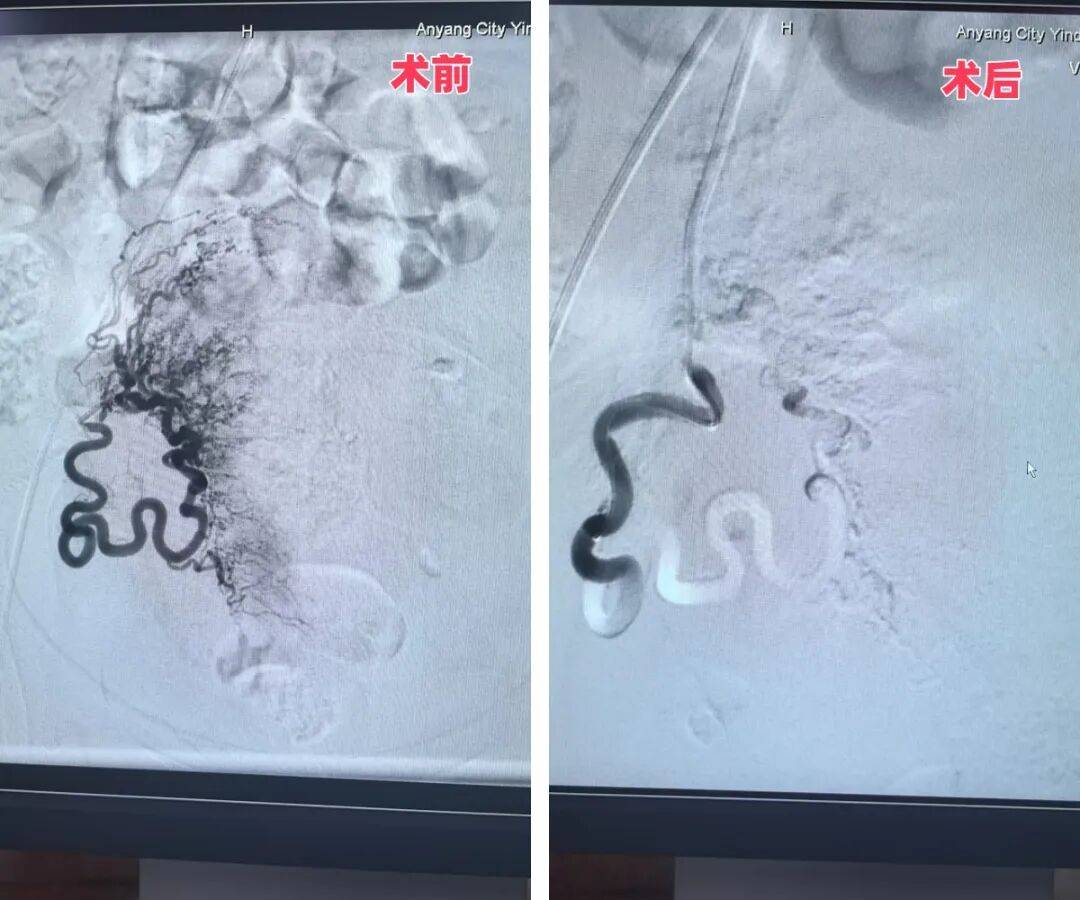

1月31日,殷都区人民医院院长、介入专家魏栋亲自操刀实施手术。凭借多年积累的丰富临床经验,魏院长精准完成双侧子宫动脉栓塞操作,全程过程顺利、定位精准,成功为患者筑起“止血防线”,大幅降低了后续手术的出血风险。此次双侧子宫动脉栓塞术,是殷都区人民医院首次将介入技术应用于妇科手术,实现了相关诊疗领域的“零突破”。

左侧子宫动脉手术前后对比图

右侧子宫动脉手术前后对比图